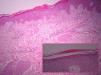

A la exploración física se apreciaban lesiones anulares eritematosas de distintos tamaños con borde discretamente sobreelevado, sin vesiculación y centro aclarado, con un collarete descamativo en el margen interno de las mismas localizadas en los muslos, el tronco y los brazos (fig. 1). Nuestro diagnóstico clínico inicial fue de eritema anular centrífugo, por lo que se solicitó una biopsia del borde de crecimiento activo de una de las lesiones. La imagen histológica mostraba un infiltrado linfohistiocitario alrededor de los vasos superficiales con zonas de espongiosis y paraqueratosis focal. La tinción PAS resultó negativa para la investigación de hongos (fig. 2). Él análisis de sangre, orina y las serologías para toxoplasma, lúes, rubéola, hepatitis B, C, y VIH fueron normales. Con el diagnóstico de eritema anular centrífugo se inició tratamiento con metilprednisolona 0,1% en crema dos aplicaciones al día, sin que las lesiones mejoraran, apareciendo algunas más progresivamente hasta el final del embarazo. Sin embargo, pocas horas después del parto las lesiones comenzaron a involucionar rápidamente, de tal forma que a los tres días posparto casi habían desaparecido (fig. 3). A los cinco días, coincidiendo con el paso del calostro a la leche materna, la paciente sufrió un rebrote que cedió rápidamente. Un mes después las lesiones habían desaparecido completamente y tras 8 meses de seguimiento la paciente permanece asintomática.